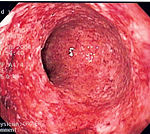

Comparison with ulcerative colitis

The most common disease that mimics the symptoms of Crohn's disease is ulcerative colitis, as both are inflammatory bowel diseases that can affect the colon with similar symptoms. It is important to differentiate these diseases, since the course of the diseases and treatments may be different. In some cases, however, it may not be possible to tell the difference, in which case the disease is classified as indeterminate colitis.

| Distribution of Disease | Patchy areas of inflammation (Skip lesions) | Continuous area of inflammation |

| Endoscopy | Deep geographic and serpiginous (snake-like) ulcers | Continuous ulcer |